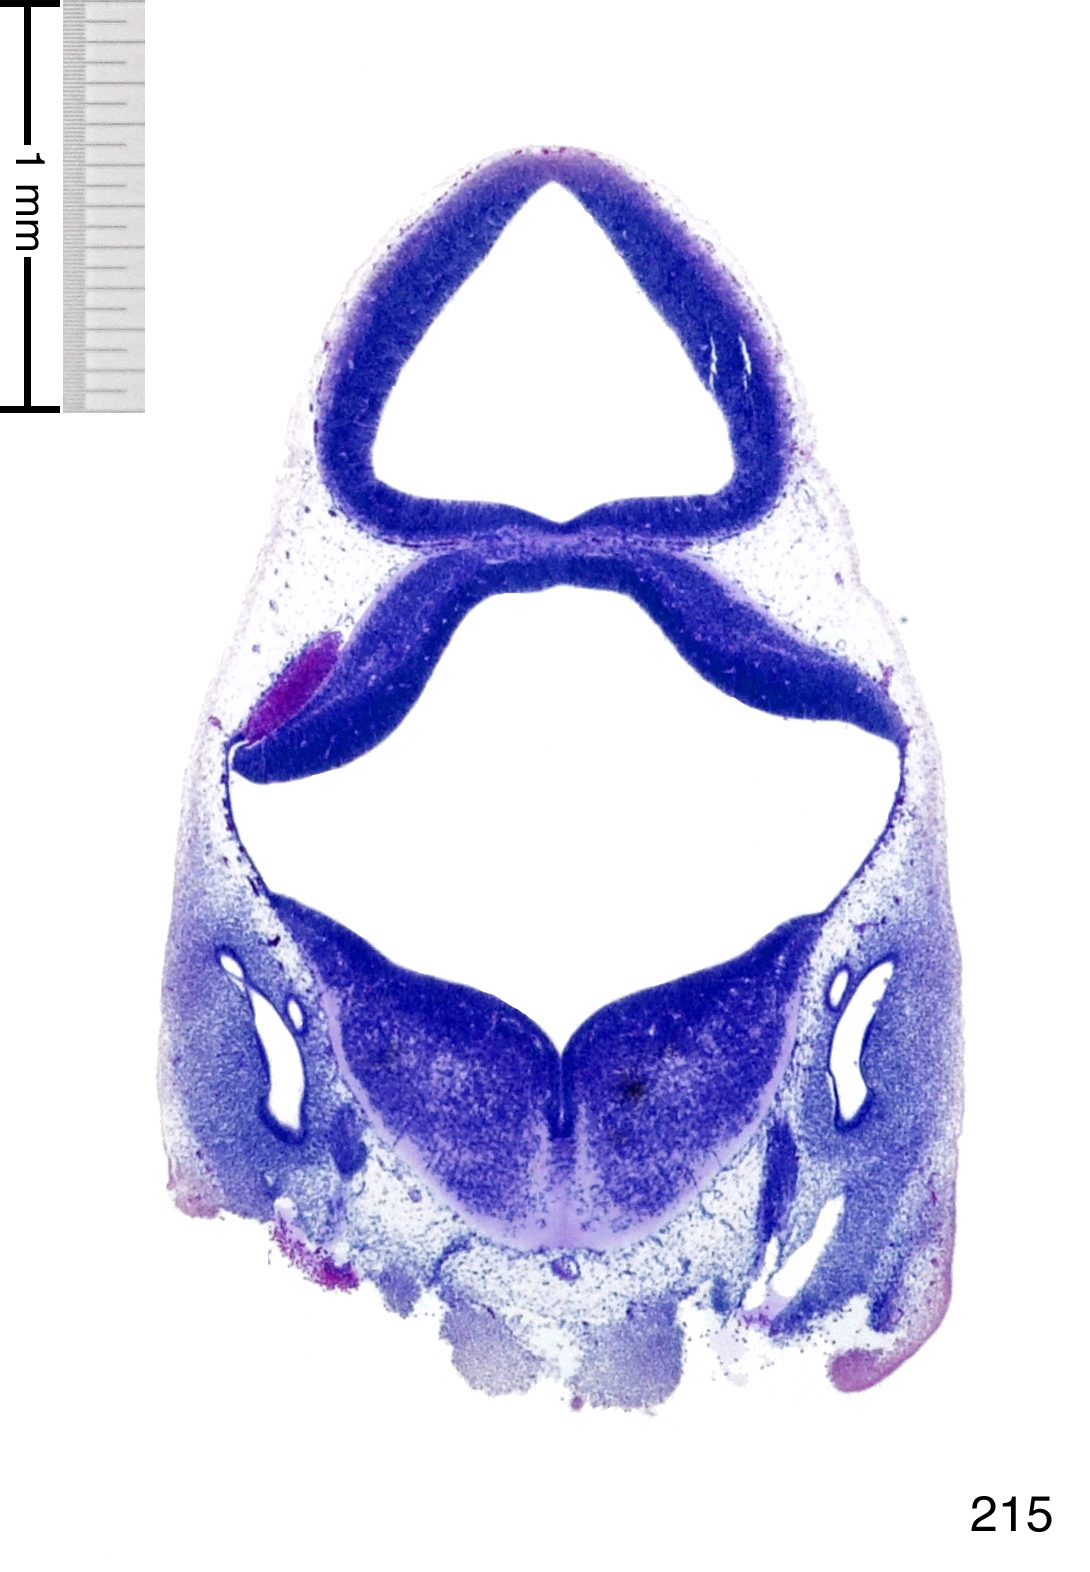

C57BL/6J GD12 Mouse Brain Atlas

Slides from U. Schambra, coronal cuts with slides at every 5th section, with a hematoxylin and eosin (H & E) stain

Currently on section 215.